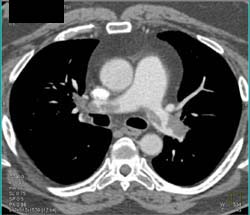

Lung Cancer Metastatic to Subcutaneous Tissue